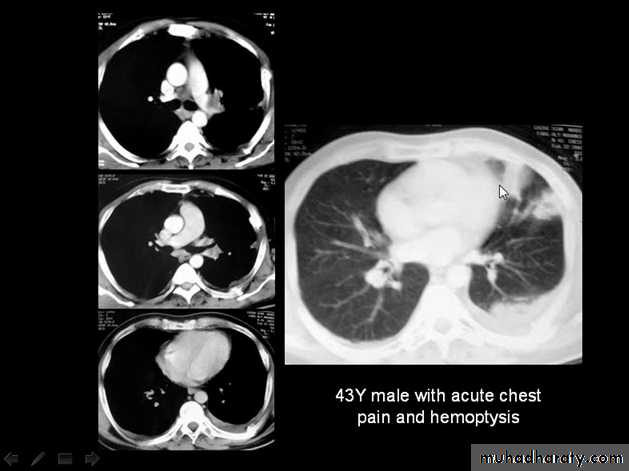

Tension pneumothorax.

On a posteroanterior chest x-ray (A), the left hemithorax is very dark or lucent because the left lung has collapsed completely (white arrows).

The tension pneumothorax can be identified because the mediastinal contents, including the heart, are shifted toward the right, and the left hemidiaphragm is flattened and depressed. A computed tomography scan done on a different patient with a tension pneumothorax (B) shows a completely collapsed right lung (arrows) and shift of the mediastinal contents to the left.

Tension Pneumothorax. Portable chest film in a 43-year-old woman with ARDS shows a large right pneumothorax with mediastinal shift and ipsilateral diaphragmatic depression, suggesting tension.

Air was evacuated under pressure during emergent placement of a right chest tube.